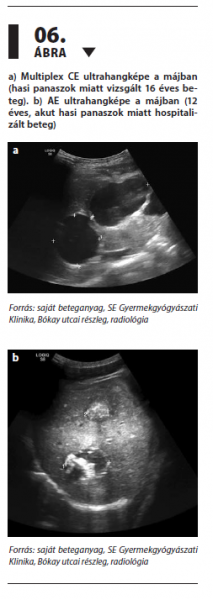

Magyarországon előforduló, gyakori féregfertőzések